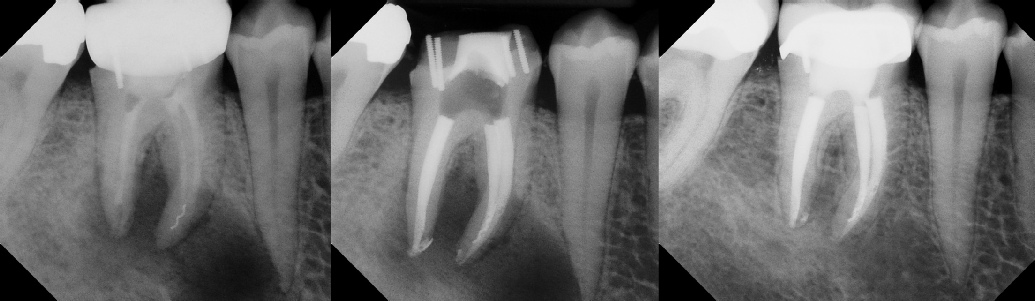

COMPLICATED ANATOMY LARGE LESIONS CALCIFIED CANALS PERFORATION / RESORPTION SEPARATED INSTRUMENTS SURGICAL CASES RETREATMENT / pOST REMOVAL OPEN APICES ACCESS THRU CROWNS Root Canal Case Portfolio

Pre-op Post-op 6 mos.